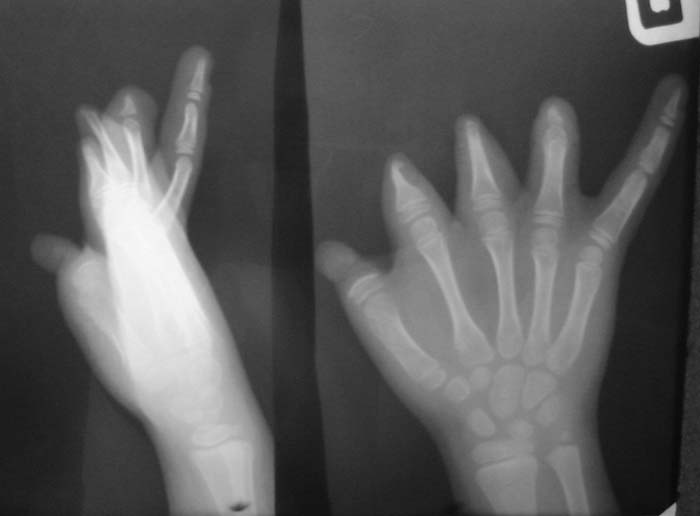

Уважаемые коллеги!Девочка, 6 лет. Врожденная аномалия развития кистей и стоп.Вопрос: лечение?В приложении - рентгенограммы и клинические фотографииЗаранее благодарен!С уважением,А.В.Владзимирский

Без рентгенограмм костей левой стопы, голени и голеностопного сустава определение тактики лечения левой нижней конечности невозможно. А с кистями рекомендую направить в специализированное отделение института им.Турнера (для удлинения фаланг пальцев с использованием микрохирургической техники)e-mail института им.Турнера: turner@admiral.ru

Исходя из возможностей современной реконструктивно-пластической хирургии

с целью восстановления функции захвата правой кисти целесообразна пересадка

пальца стопы в позицию первого луча. В этом случае пересадка второго пальца

левой стопы невозможна из-за аплазии донорской зоны. Поэтому здесь допустимо

произвести реконструкцию области дефекта пересадкой второго пальца левой

стопы. Необходимо учитывать и этиологию дефекта - врождённая аплазия, что

является одним из противопоказаний к реконструкции - отсутствие корковой

интеграции. Учитывая возраст больного это противопоказание условное. В таких

случаях, по литературным данным, допустимо проведение реконструкции до

десятилетнего возраста - возможность перестройки цереброкортикальной

интеграции при условии проведения соответствующего реабилитационного

лечения.

Пациенту необходимо воосстановить опорную функцию правой нижней

конечности.